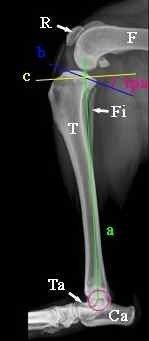

- rekonstruktive Operationen während gebrochene Knochen Gliedmaßen mit Stiften, Platten und Schrauben.